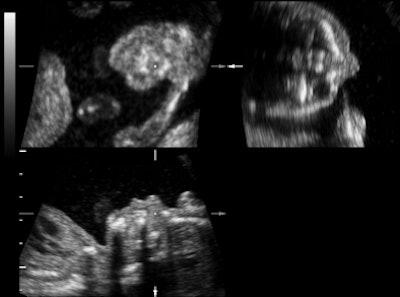

| Representative fetal profile images showing good-quality (above), acceptable-quality (below), and poor-quality (bottom) images. All images courtesy of the Journal of Ultrasound in Medicine. |

![]() |